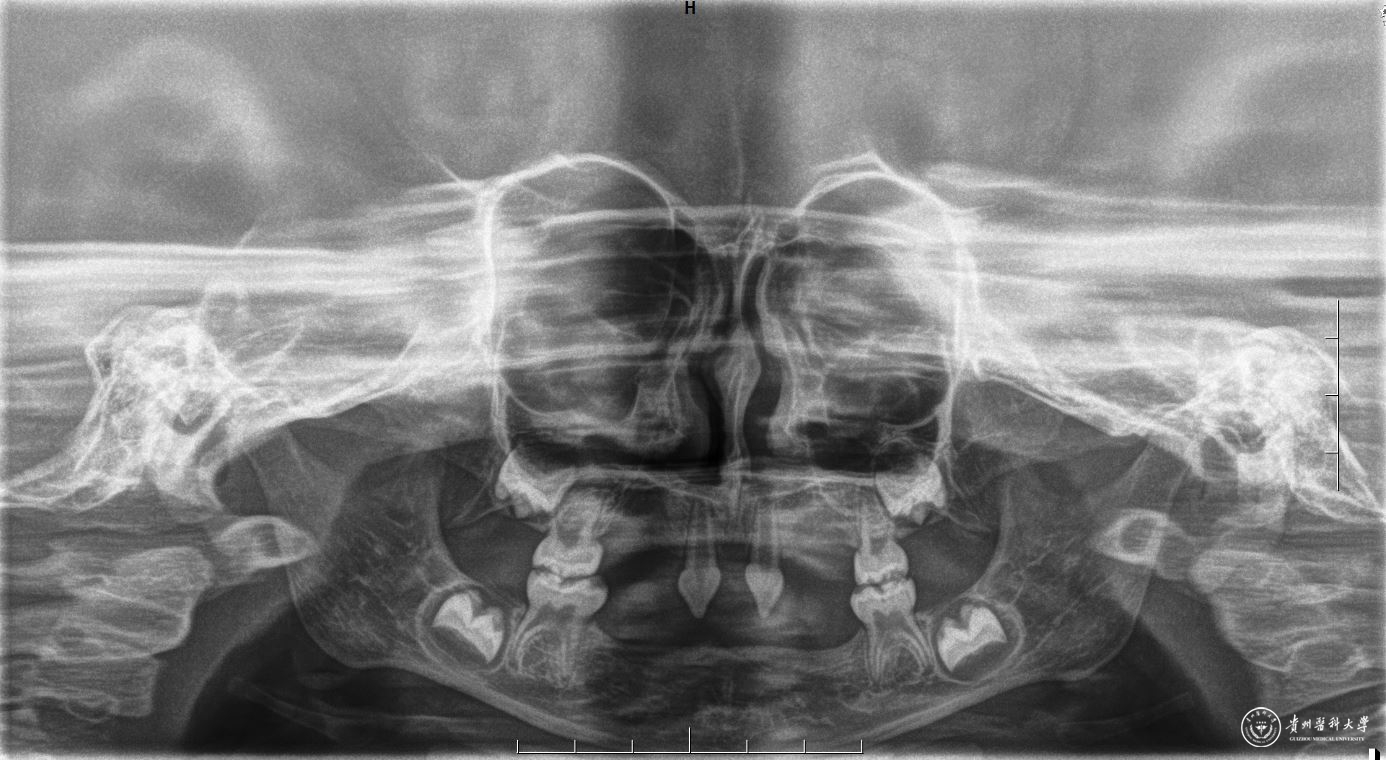

2月22日,附属口腔医院口腔修复种植科为一位4岁患儿完成罕见的外胚层发育不全可摘局部义齿修复,该患儿为目前医院完成修复治疗年龄最小的患者。

患者4岁,不能正常咀嚼,于2022年底在外地就诊多次无法修复后,专程到口腔医院就诊。医院细心商讨诊疗方案,于2月22日由王永带领谭雯珈、姜炜鹏等医师,使用修复、正畸、修复工艺等多项技术,顺利完成了大面积乳牙缺失修复,患儿现场进食效果良好,家长及患儿十分满意。

因其口腔表征为先天缺牙甚至无牙颌,且缺牙患儿口内余留牙往往表现为锥形牙、釉质发育不良、牙槽嵴发育不良等,可严重影响患儿的咀嚼功能及面部软硬组织生长发育。